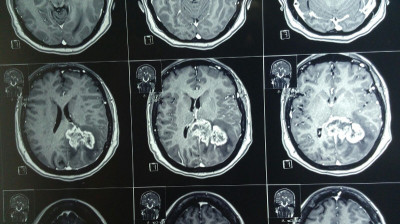

Paciente femenina de 55 años con tumoracion pineal con extencion superior lateral derecha